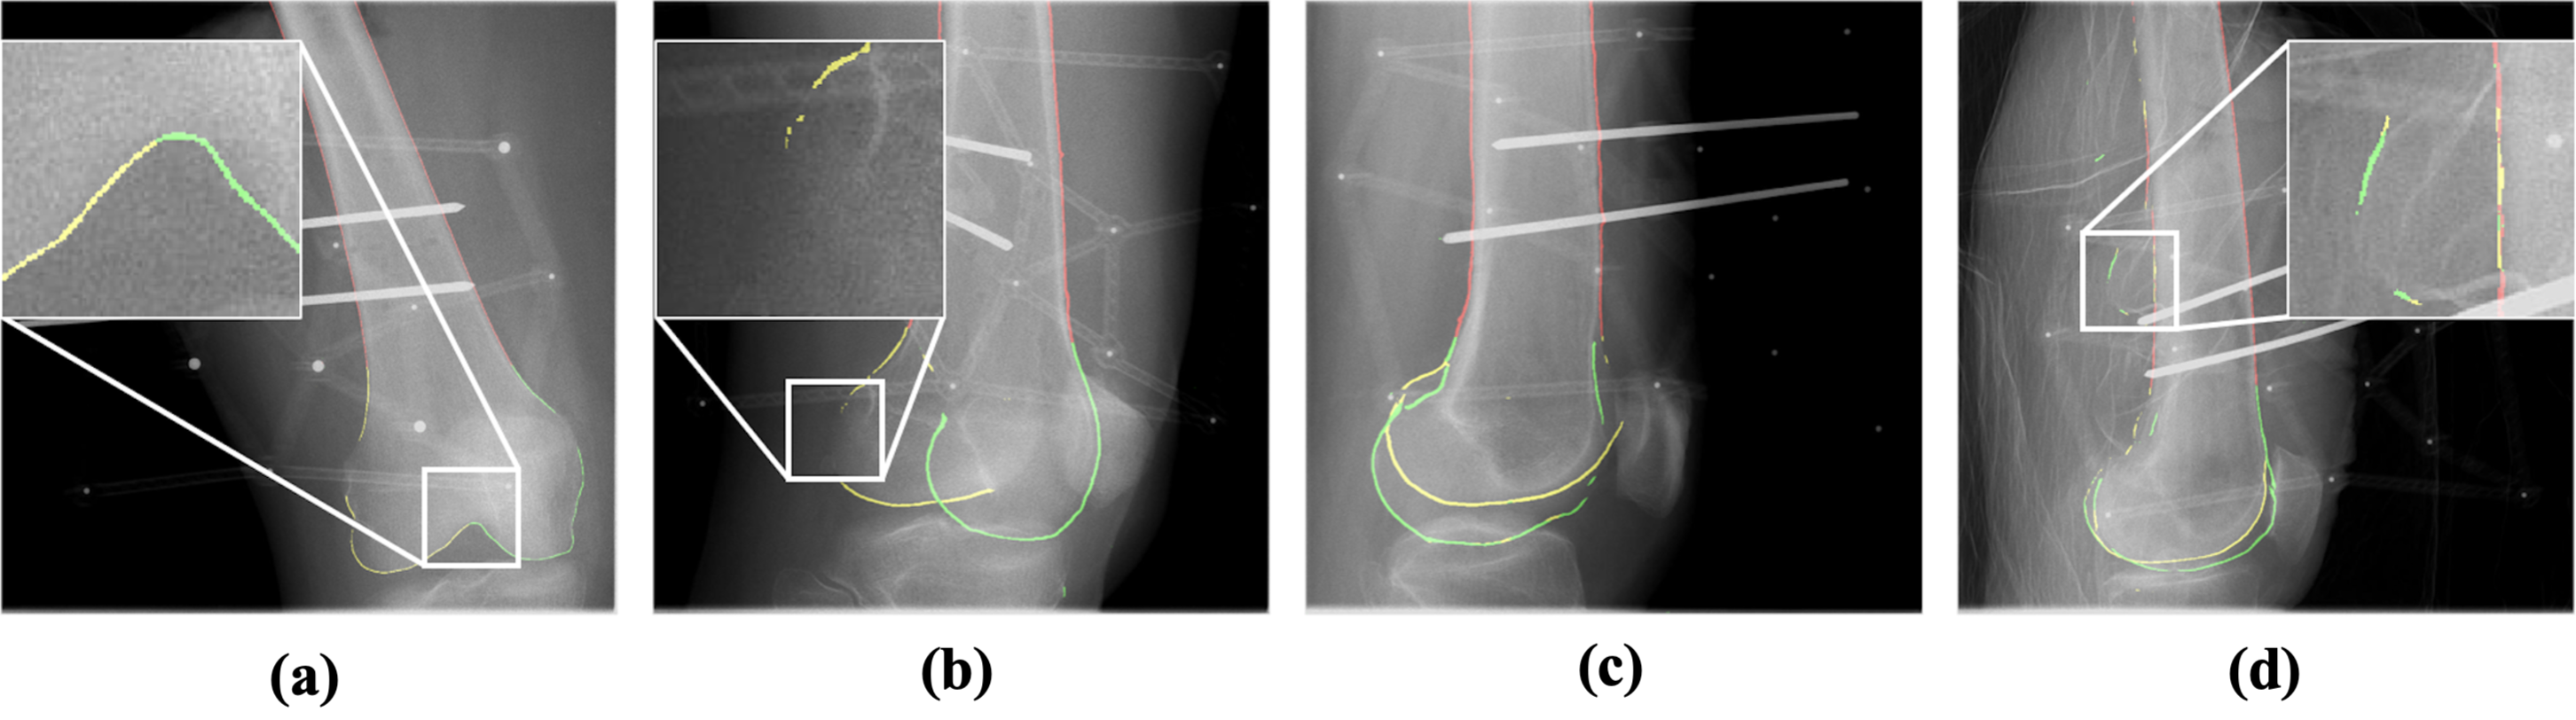

Registration An evaluation of multiple registration strategies was performed. The commercial intensity-based method ImFusion [6], which is considered a leading approach in multi-view intensity-based registration. This method requires manual initialization to function effectively. Corresponding landmarks are manually placed by clicking correspondences in the images and CT data to achieve a rough alignment of the bone. Specifically, four corresponding points are manually marked in the images and CT using the provided GUI. These correspondences are then used to initialize the registration, bringing it close to the final solution. All registration parameters were kept at their default settings during this process. Additionally, we included a related ICP and contour-based approach from Zhang et al. [9], with improvements by replacing Canny edge detection [21] with a deep-learning-based edge detection method [22] in our implementation of the method. This method utilizes the bone silhouette, without any semantic substructures, during optimization. We did not find more open-source implementations of multi-view registration methods. Table 4 summarizes the registration errors on our real-world dataset. For each registration, we used two views with a perspective change of at least 45 degrees. Since our method does not require initialization, we set fixed values for all experiments, i.e., translations of +30mm, -40mm, +5mm and Euler angles of -17.18°, 0°, 17.18°. There are a total of 30 runs (6 runs per subject 5 subjects) presented for each method. As described in Section 4.2, we use the mRPD as evaluation metric. The evaluation setup consisted of 3 control views, seperated by 9° each situated in between the two X-ray images used for registration. Our method achieved an mRPD of 0.67mm, compared to 5.35mm for the commercial method and 4.03mm for Zhang’s method. In some cases, our method produced incorrect registrations. We demonstrate empirically in Online Resource 1 that these failing registrations can be automatically detected using the reprojection errors during the ICP optimization, allowing the registration to be restarted. Note that this property holds under certain conditions regarding the quality of the contour segmentation results.

Impact of Occluding Contours A key innovation of our method is the use of component-level contours, as described in Section 3. Their benefit in the ICP optimization is significant when compared to the object-level contours in Zhang’s method, as shown in Figure 4 and Figure 5. Zhang’s method, which does not incorporate substructures, is more prone to getting trapped in local minima, as shown by the larger errors compared to our method.

Visual Results Figure 6 shows a qualitative comparison of our method with ImFusion. Green contours represent the ground truth, and the colored dots show reprojected points from the registered decimated bone mesh.